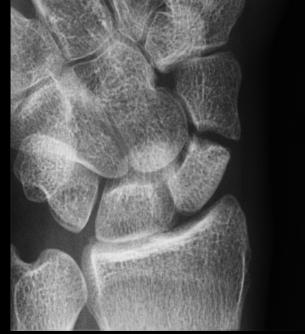

Xray

Nonunion with minimal displacement and minimal resorption

Nonunion with significant displacement and bone resorption

Proximal pole fracture with displacement and absorption